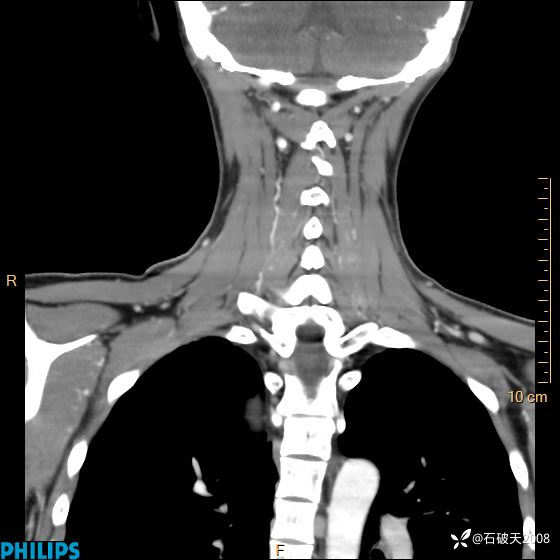

影像诊断要密切结合临床,真的很有必要(病理已公布)

女 21岁 主 诉:发现右侧颈部肿物18年余。

现病史:18年余前患者无明显诱因发现颈部偏右侧有一肿物,具体大小不明确,咳嗽、憋气时肿物增大,局部无疼痛,无吞咽不适,无胸闷及呼吸困难,至当地医院检查考虑良性病变(具体不详)并未做特殊处理,现患者自觉肿物随年龄增长而进一步变大,今日至我院行颈部CT平扫+增强提示:1.右侧颈根部、锁骨上窝及纵隔内异常密度影,考虑良性病变,淋巴管瘤?囊肿?请结合临床。2.双侧颈部小淋巴结。建议结合临床及其他相关检查。现为行进一步治疗,门诊以“颈部局部肿物”为诊断收住我科,发病来患者神志清,精神可,饮食睡眠可,大小便正常,体重无下降。

冠状位